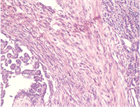

1. 早期の胸膜中皮腫と反応性中皮細胞増生(反応性中皮過形成)の病理像は類似し、良悪の鑑別は慎重に行う必要がある。BAP1免疫染色、CDKN2A遺伝子の中皮腫でのホモ接合性欠失の検出が鑑別に役立つ。